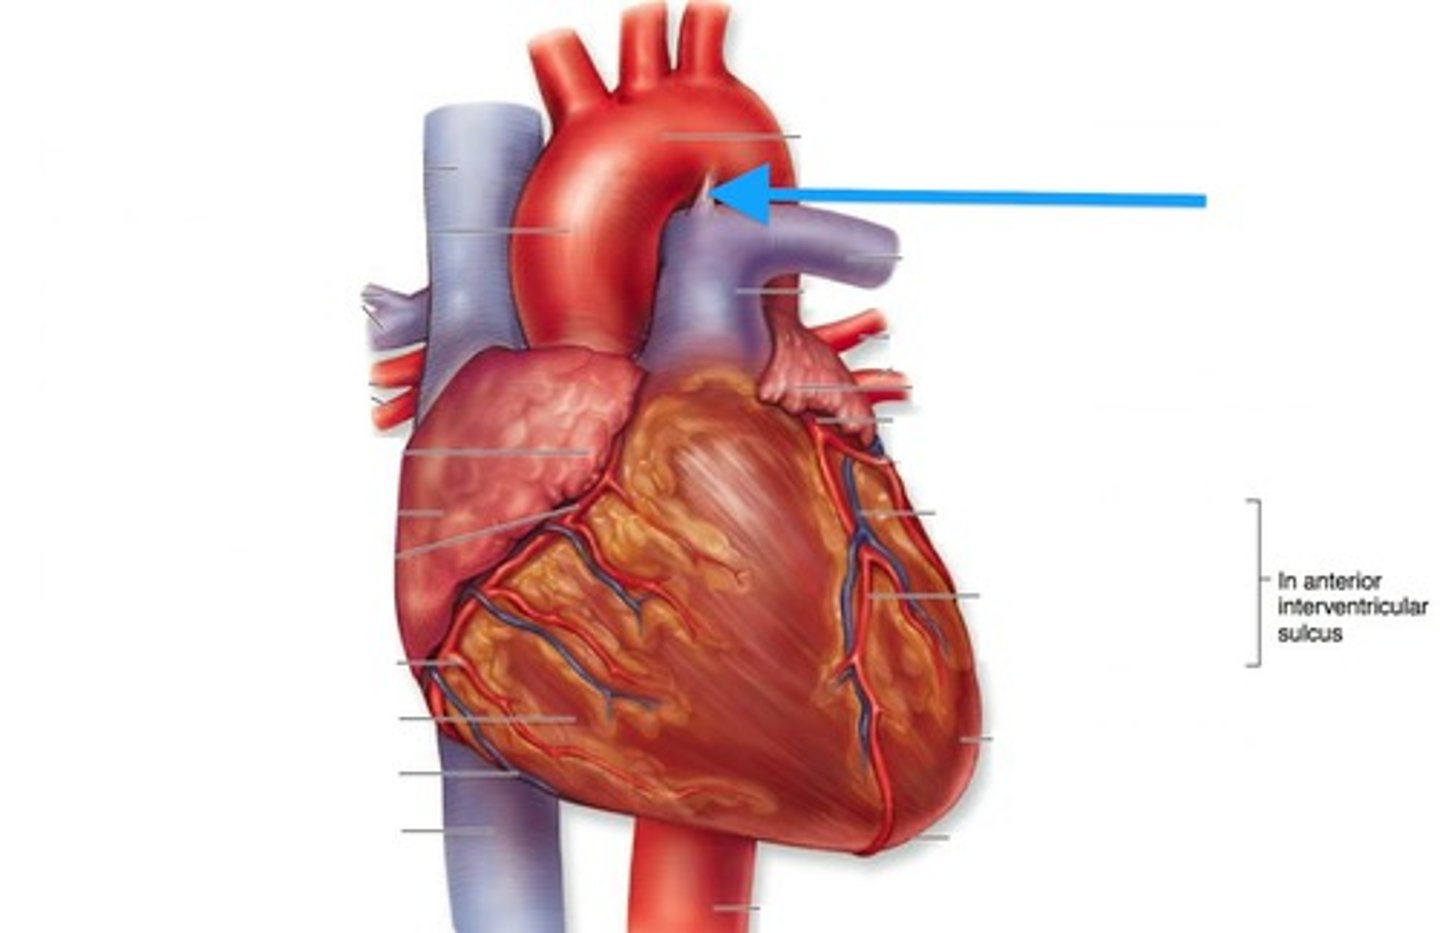

ligamentum arteriosum

webbing connecting aorta and pulmonary trunk

12

BQ: vestige of the fetal ductus arteriosus, which shunted blood in the pulmonary trunk away from the lungs in the fetus